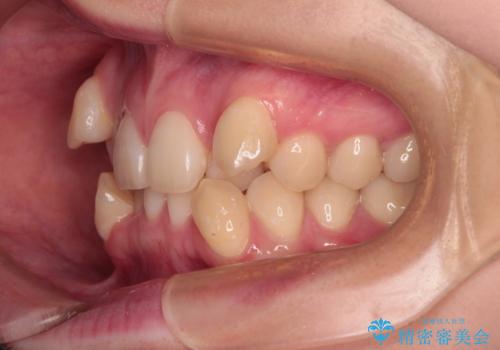

上下の八重歯とクロスバイト ワイヤー装置での抜歯矯正

- 八重歯とクロスバイトを気にして来院された患者様です。

上下ともに八重歯が顕著であり、前歯のクロスバイトがあったため、上下左右の第一小臼歯4本を抜歯し、ワイヤー装置での抜歯矯正を行うこととしました。